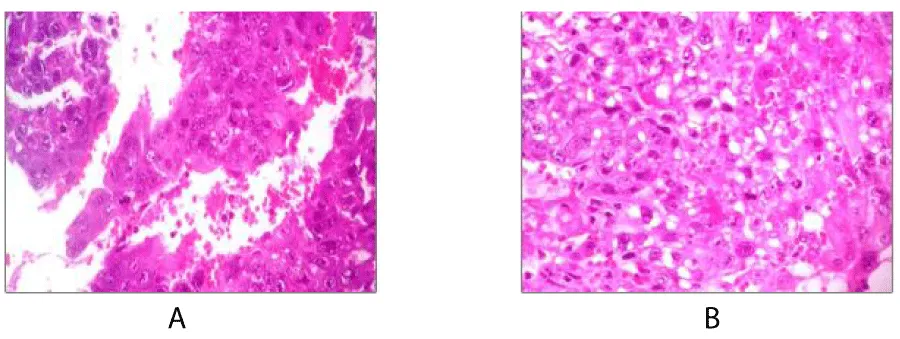

On physical examination, the patient with generalized pallor of the skin and integuments, hypotensive, tachycardic, diaphoretic, without cardiorespiratory compromise, globose abdomen due to abundant adipose panniculus, perstalsis present, pain on palpation in the right iliac fossa on bimanual touch, the uterus is delimited 8x5 cm, right annex, 12x9 cm adnexal tumor, irregular, firm, pain on cervical mobilization, with spotting-shaped transvaginal hemorrhage, extremities without edema, normal tendon reflexes. According to the clinical presentation, imaging studies, on suspicion of ruling out ectopic pregnancy, an exploratory laparotomy was performed, with findings of the right annex of 20x15 cm adhered to the uterus and sigmoid rectum without evidence of hemoperitoneum and a right salpingo-oophorectomy was performed for probable right ectopic pregnancy with hematic loss due to the surgical procedure of 40cc and sent to pathology for definitive histopathological study, during follow-up a control gonadotropin quantification was requested with the last report of 1 103 918.7 mUI/mL. The histopathological results of the macroscopic surgical specimen were right salpingo-oophorectomy, with choriocarcinoma with extensive necrosis, 1 cm tumor extension to the ovarian surface not identified, lymphovascular invasion present and free surgical margins of the residual ovarian tumor with cystic follicles, Figure 1 and the report microscopic, Figures 2-4. A new hCG quantification is performed, negative head tomography and chest tomography with probable metastasis due to pulmonary nodule, in abdomen and pelvis, presence of peritoneal carcinomatosis, with free fluid and lumbar puncture reports negative for malignant cells and chemotherapy based on cisplatin and etoposide 5 sessions and the patient is disease-free after two years of follow-up.